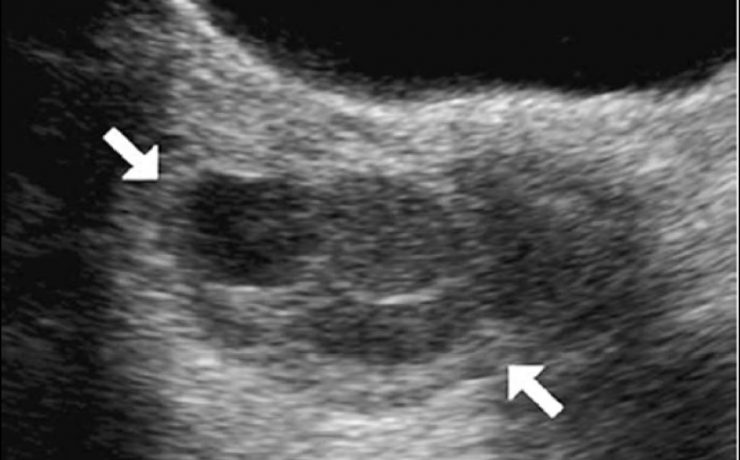

El signo del lirio caído , fue descrito hace más de 40 años en pielografía de eliminación y corresponde al aspecto que adquiere el sistema pieloureteral inferior en un riñón con doble sistema excretor, dado por una pelvis renal de orientación horizontal y cálices que se dirigen discretamente hacia cauda.